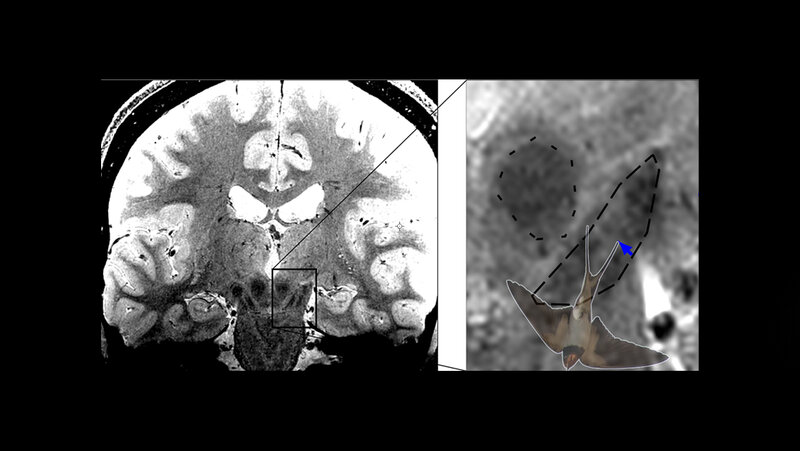

Bei Parkinson sterben dopaminproduzierende Nervenzellen in der Substantia Nigra im Mittelhirn ab, was bei den Betroffenen zu Bewegungsstörungen wie Verlangsamungen, steifen Muskeln und Zittern führt. Besonders stark und früh sind die Nervenzellen im Nigrosom 1 innerhalb der Substantia Nigra betroffen. Mit hochaufgelöster MRT-Bildgebung ist die Abbildung des Schwalbenschwanzzeichens möglich, welches sich im hinteren Drittel der Substantia nigra befindet und nach gängiger Lehrmeinung Nigrosom 1 entspricht. Bei gesunden Menschen erkennt man im MRT-Bild eine signalreiche längliche Struktur, die vorne und an den Seiten von signalarmen Arealen umgeben ist. Diese besondere Form erinnert an einen Schwalbenschwanz, daher spricht man auch vom Schwalbenschwanzzeichen (engl. Swallow tail sign). Nach der gängigen Interpretation des Zeichens führt das Absterben der Neuronen im Nigrosom 1 bei Parkinson-Betroffenen dazu, dass das Schwalbenschwanzzeichen schließlich nicht mehr erkennbar ist. Ist das der Fall, liegt mit hoher Wahrscheinlichkeit eine Parkinson-Erkrankung vor.

Malte Brammerloh und seine Kolleginnen und Kollegen haben nun mikroskopische 3-D-Untersuchungen von menschlichen Gehirnen nach dem Tod mit MRT-Technik kombiniert, um zu zeigen, dass Nigrosom 1 und das radiologische Schwalbenschwanz-Zeichen sich nur teilweise überlappen und in der Tat sehr unterschiedlich sind. Die Wissenschaftler/-innen plädieren daher dafür, das Schwalbenschwanz-Zeichen nicht mit der Region Nigrosom 1 gleichzusetzen. Dies erlaube eine Neuinterpretation des diagnostischen Schwalbenschwanz-Zeichens und eröffne gleichzeitig neue Wege zur spezifischen Nigrosombildgebung. Brammerloh ist sich sicher: „Wir glauben, dass man mit diesem neuen Wissen besser versteht, wie Anatomie und MRT-Kontraste zusammenhängen und wie neue MRT-Marker für die frühe Diagnose von Parkinson entwickelt werden können.“